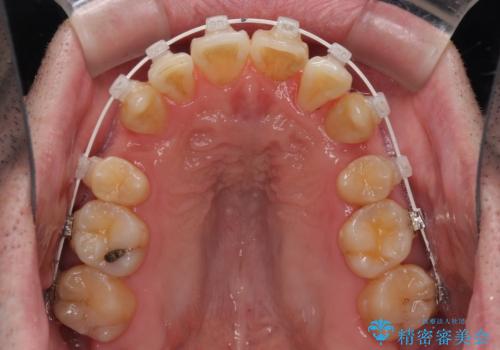

ものが挟まる 著しい叢生を解消 ワイヤー装置による抜歯矯正

- 審美装置

- 前歯のデコボコを気にして来院された患者様です。

叢生の解消とともに、前方に張り出した上顎前歯を引っ込めることを目的とし、上下左右の第一小臼歯4歯を抜歯をしてワイヤー矯正により治療することとしました。

治療開始直後は、あっという間に歯列が整い、すぐに終わるのではないかと思われましたが、治療の後半にブラックトライアングル解消のための処置を行ったため、当初予定していた2年半ほどの期間を要することとなりました。